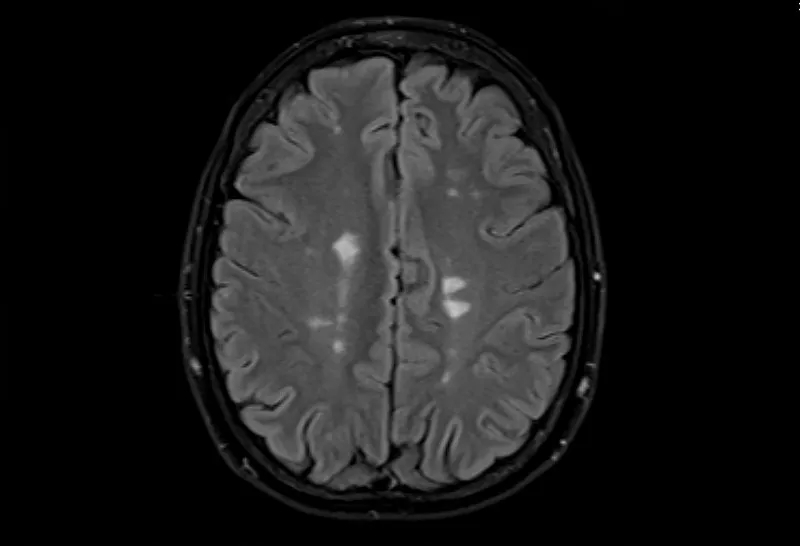

- 大腦的MRI掃描可以顯示損傷區域,但沒有單一的測試可以診斷MS。

測試的組合用于診斷MS。最好的測試是對您的大腦和脊髓進行核磁共振檢查,以檢測損傷區域。您可能還需要進行血液檢查、腰椎穿刺和測量神經活動的測試。